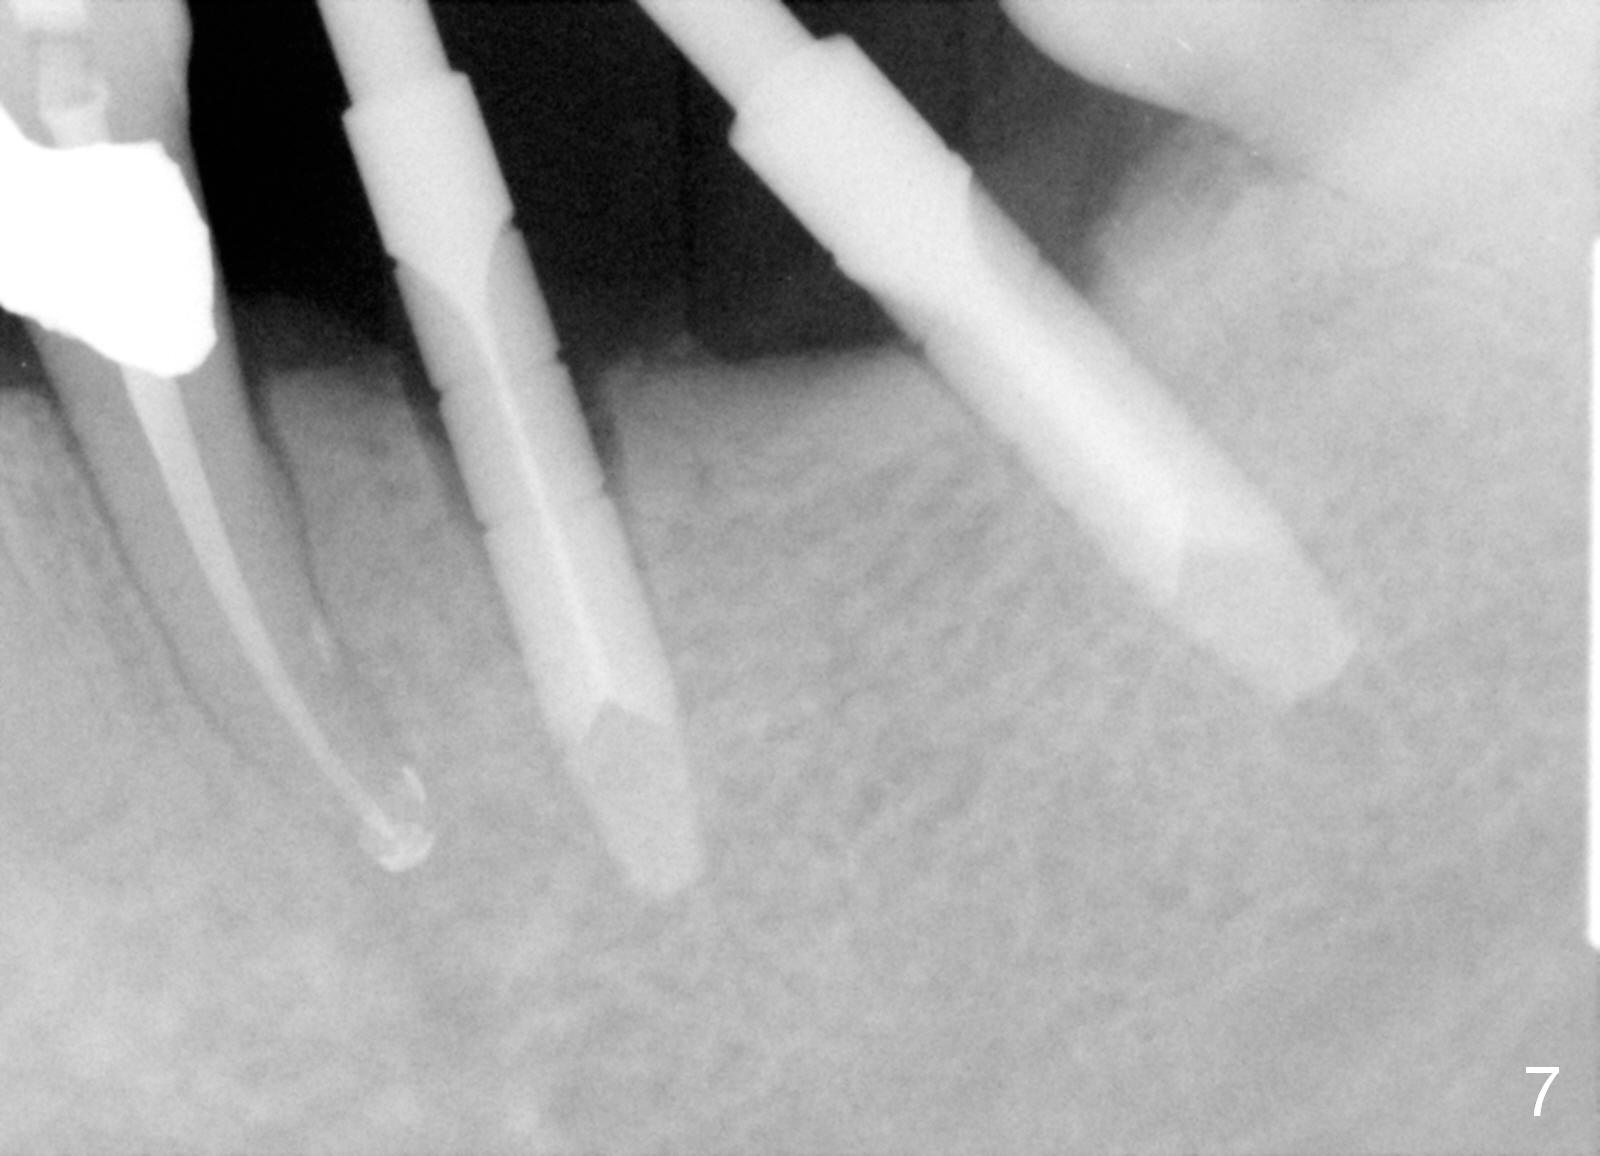

One year 2 months post root canal therapy at #20 (Fig.4), osteotomies are initiated at #18 and 19.  The trajectory at #19 is subsequently corrected (Fig.5); that of #18 should be also corrected (arrow).  The fact of the narrow ridge (Fig.6) is also ignored intraop.  Without further adjustment, the osteotomies are enlarged (Fig.7) and the implants are placed (Fig.8: 4.5x14, 5x14 mm).  As expected, the buccal coronal implant surface is exposed.  The buccal plate is decorticated with placement of autogenous bone graft.  Periodontal dressing is applied.  Postop, the wound is infected with wound gapping.  With irrigation, the wound finally heals.